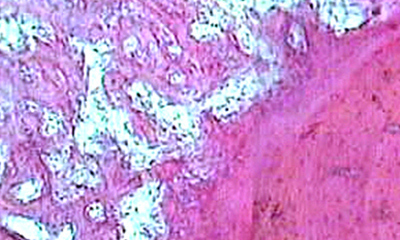

Важным условием для течения любого раневого процесса, в том числе и в костной ране, является завершенное течение фазы воспаления и создание условий для нормализации процессов энергопродукции и появления возможности для избыточного анаболизма. На временные критерии возникновения этого состояния значительное влияние оказывает состояние кровообращения в области повреждения и всем сегменте конечности в целом. Развивающаяся в результате травмы дезинтеграция кровоснабжения приводит к нарушению оксигенации тканей. Выраженность и протяженность области сосудистых нарушений, дестабилизации ультраструктур микроангиоархитектоники и особенно путей оттока крови находится в прямой зависимости от энергии травмирующего агента. Прогрессирование дистрофических процессов в тканях конечности после травмы в значительной мере зависит от посттравматических микроангиопатий, развивающихся на фоне нарушений в венозном отделе микроциркуляторного русла, что приводит к формированию трансэндотелиальных каналов и люков, плазматическому пропитыванию стенки сосудов, ее гиалинозу и склерозу. Вследствие этих изменений возникает нарушение транскапиллярного обмена, нарастает гипоксия и существенно ухудшается трофическое обеспечение тканей конечности. Наряду с этим, снижение объемного уровня кровотока в микроциркуляторном русле поврежденного участка приводит к нарушению информационных процессов между зоной повреждения и лимфоидными органами и, как следствие, замедлению или редукции течения воспалительного процесса. На длительность стадии разрушения и дедифференцировки клеток значительное влияние оказывает дисбаланс энергетических процессов. В результате гипоксии в поврежденных тканях нарушается соотношение циклических нуклеотидов (цАМФ и цГМФ), посредством которых реализуется воздействие нейрогуморальной регуляции биохимических процессов в клетке. Вследствие этого нарушаются регуляторные механизмы процессов энергопотребления в клетке – они не соответствуют скорости энергопродукции. Результатом энергетического дисбаланса является преобладание эрготропных процессов над трофотропными и превалирование процессов ассимиляции над диссимиляцией.